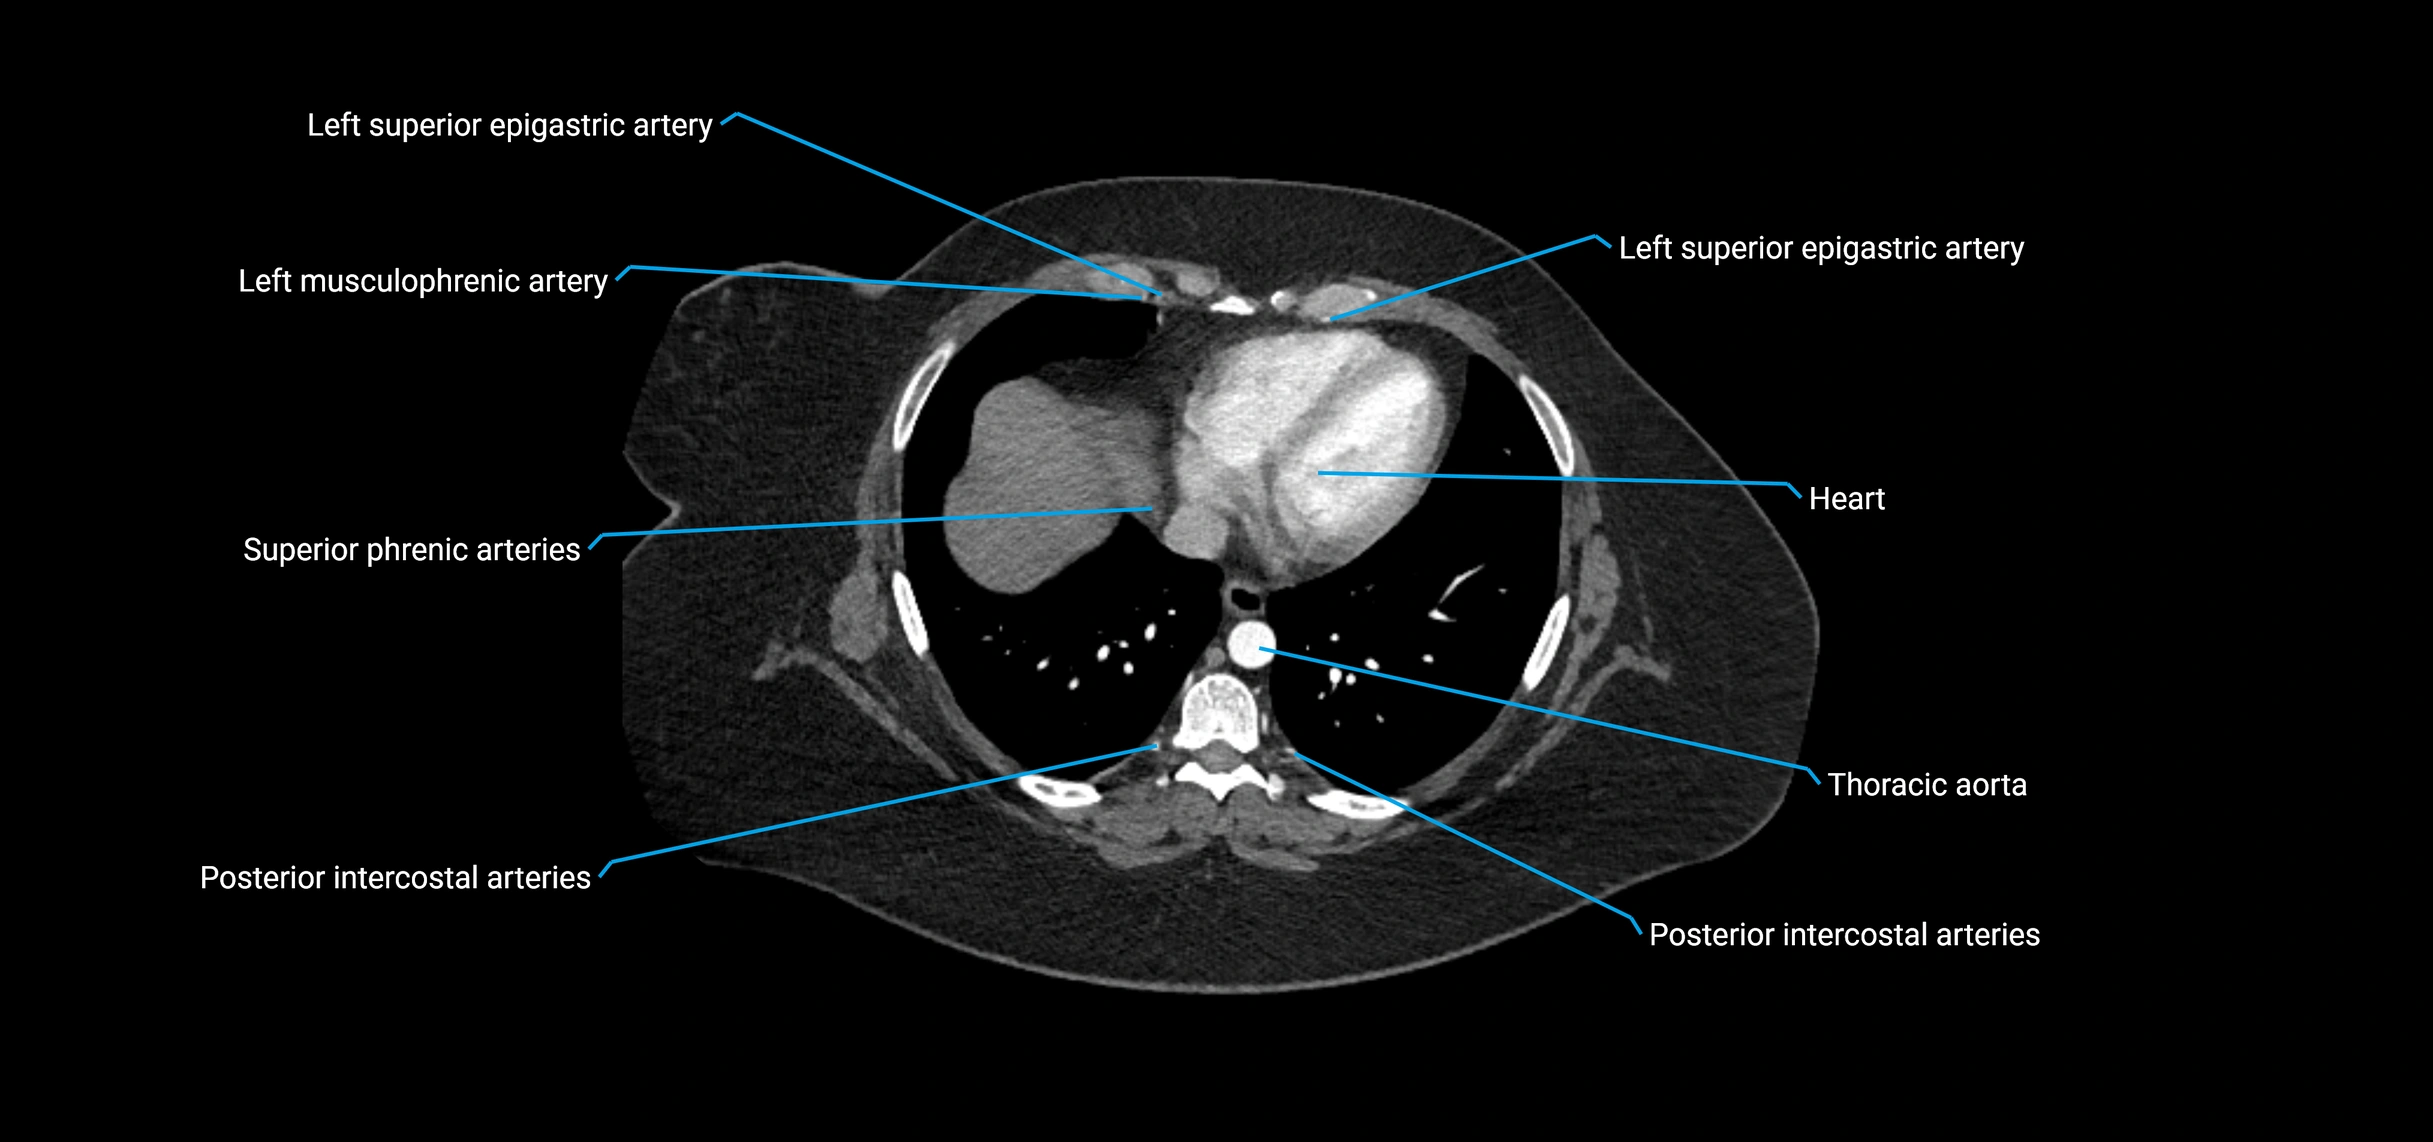

CT Appearance

Non-contrast CT:

• Appears as a tubular soft tissue structure anterior to vertebral bodies

• Calcified atherosclerotic plaques appear as hyperdense foci along the wall

• Useful for screening abdominal aortic aneurysm (AAA) size and mural calcification